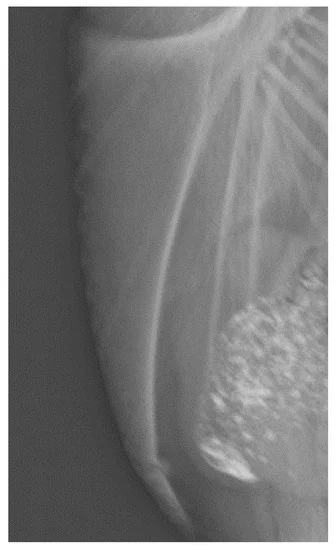

这是一次骨折的龙骨(30 周龄):